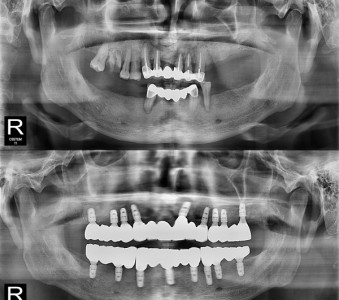

以成果证明实力。

国际摩牙齿科

真实临床案例